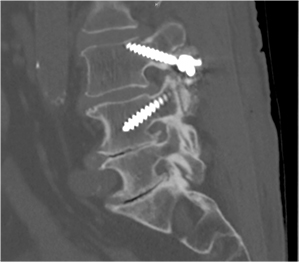

- We recommend a postoperative CT (Figs 4,5) to check

that the MLST screw is within the confines of the

pedicle.

Fig. 4 Lateral radiograph showing the trajectory of an MLST screw in

L3, starting at the pars with the screw angled towards the lateral

aspect of the endplate. Note the L4 pedicle screw is angled in a

superior-inferior direction, the opposite of the MLST screw.